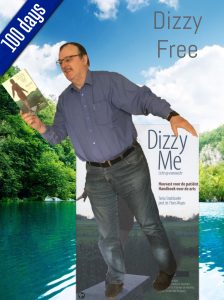

Jaaaaaa daar is ie dan. Het lang verwachte boek Dizzy Me.

Wat is het een spannende periode geweest vanaf de crowdfunding tot de uitgave van deze editie. Bloed, zweet en tranen, maar de auteurs van de Engelse editie van Dizzy Me, Tania en Floris, zijn erin geslaagd om een meesterwerk neer te zetten. Een handzaam boekwerk boordevol met actuele informatie. Een boek die thuishoort op de boekenplank van iedere KNO- of NPO-arts, waar ook ter wereld. Ze moeten er ook natuurlijk kennis van nemen, niet er alléén in ‘neuzen’. Medische studenten in opleiding moeten het als standaard werk bij zich hebben. Als dit allemaal gerealiseerd kan worden ziet de wereld van een patiënt, die een evenwichtsstoornis heeft, er een stuk evenwichtiger uit.

Ik kwam in 2015 de Nederlandse editie van dit boek op het spoor.

Na 5 jaar misdiagnoses door de KNO-artsen van het MCL te Leeuwarden werd door Professor dr. Floris Wuyts de juiste diagnose gesteld: Vestibulaire Paroxysmien (VP). Nu al ruim 400 dagen Dizzy Free.

Het is vandaag precies 100 dagen geleden dat ik voor het laatst een evenwichtsstoornis heb gehad. Het gaat nu prima en ik ben actiever geworden.

Het is vandaag precies 100 dagen geleden dat ik voor het laatst een evenwichtsstoornis heb gehad. Het gaat nu prima en ik ben actiever geworden.Wat eraan vooraf ging……

Door het lezen van het boek Dizzy Me kwam ik er achter dat men bij het UZA te Antwerpen ver waren m.b.t. het onderzoeken naar evenwichtsstoornissen en het stellen van een juiste diagnose. Ik heb toen gevraagd om mij door te verwijzen naar het UZA, alwaar ik werd geholpen door professor dr. Floris Wuyts. Na onderzoek en gebruikmakende van de SO STONED methodiek stelde de professor bij mij de diagnose Vestibulaire Paroxysmien (VP). Door het innemen van de medicatie Carbamazepine zijn de evenwichtsstoornissen drastisch afgenomen. Het is de bedoeling dat ik in het voorjaar van 2017 de medicijnen ga afbouwen en weer een bezoek aan professor dr. Floris Wuyts ga brengen.

Het is van groot belang dat de patiënten en medici kennis gaat nemen van het boek Dizzy Me. Er lopen te veel patiënten rond in de wereld die een misdiagnose hebben en eerder zieker worden dan beter.

De Engelse versie verschijnt juni van dit jaar, evenals een Engelse E-book. Later dit jaar verschijnt er ook een Spaanse uitgave.

Floris Wuyts en Tania Stadsbader zijn de auteurs van het boek Dizzy Me. Een houvast voor de patiënt en een handboek voor de arts.

Tania kampte vijftien jaar met evenwichtsstoornissen. Pas na een operatie raakte ze van haar aandoening verlost. Het boek geeft een beeld van haar lange zoektocht naar de juiste diagnose en de impact en naweeën van jaren ziek zijn. Tania brengt haar verhaal heel direct en geeft lotgenoten een stem. Floris Wuyts maakt het boek helemaal af met zijn wetenschappelijke benadering en de meest recente bevindingen.

Deze baanbrekende mix van patiënt en prof maakt dit boek uniek in zijn soort.

Kijk ook op www.dizzyme.eu.